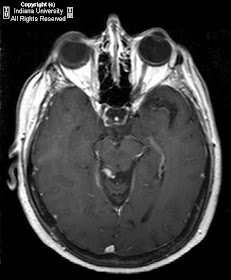

Along the posterior aspect of the midbrain there is exophytic focus of hyper intense T1 and heterogeneously hyper intense T2 signal which is heterogeneously hypo intense on T2 with fat suppression. This small mass heterogeneously enhances on T1.

Diagnosis: CNS dermoid.